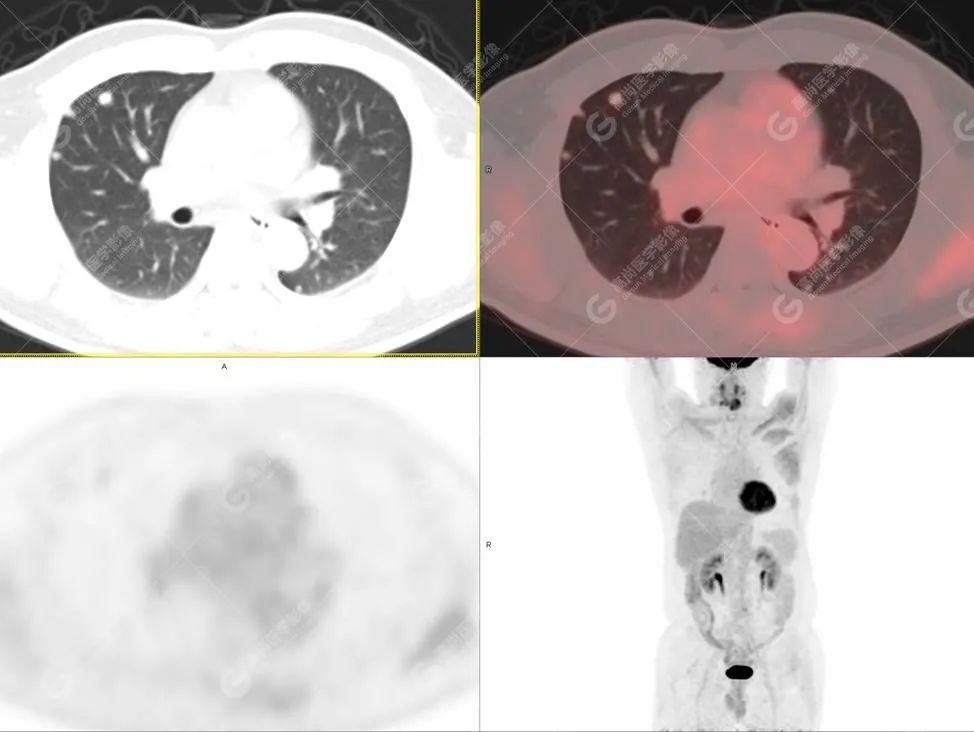

PET/CT影像图

图1

PET/CT检查

影像诊断: 1.舌体部左右侧软组织明显增厚,密度稍低,左侧为著,代谢异常增高, 考虑为舌癌,并口底受侵, 建议穿刺病理学检查明确。

2.双肺多发大小不等实性结节,部分代谢轻度增高, 考虑为转移瘤。